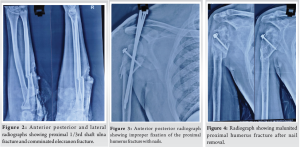

A 31-year-old male visited our outpatient department with complaints of right elbow pain on movement and restricted movements affecting his activities of daily living. He gave a history of road traffic accident 2 years before in which he had sustained a right-sided severely comminated proximal humerus fracture (Fig. 1) and right-side compound ulna proximal third shaft fracture with olecranon comminated fracture (Fig. 2). He underwent open reduction and fixation for proximal humerus (Fig. 3), olecranon and ulna fracture. 12 months post-surgery the proximal humerus implants were removed and the fracture was malunited (Fig. 4).